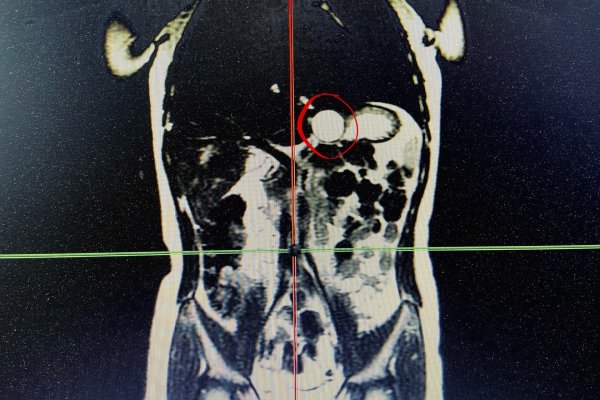

Врачи прооперировали врожденный порок развития желудка.

59-летняя жительница Сыктывкара смогла кардинально улучшить здоровье благодаря комплексному изменению образа жизни.